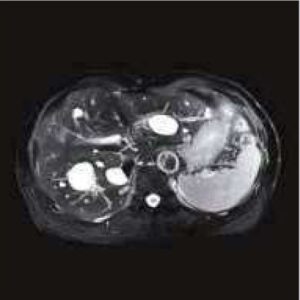

Body Imaging

The Body Suite is specialized for Clinical body examinations.